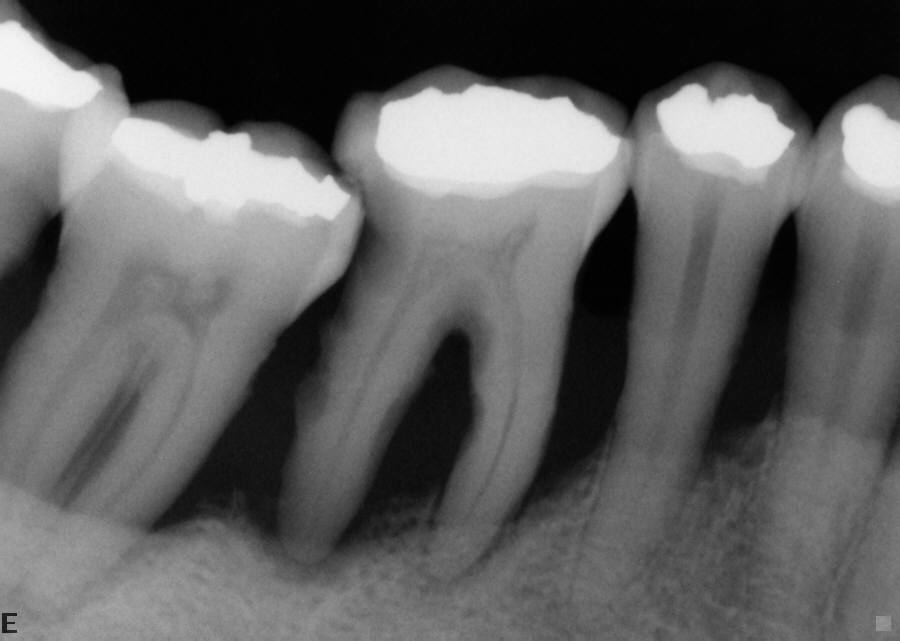

From www.seattle-endo.com

Maxillary Sinusitis of Endodontic Origin (MSEO) Seattle Endodontics Dental Periostitis One of the most annoying conditions is dental periostitis also known as gumboil. Chronic osteomyelitis with proliferative periostitis is a rare form of osteomyelitis that is characterised by new. The most common cause for po is periapical infection of mandibular first molar. Depending on the type and complexity of periostitis, the dentist will treat tooth canals or correct dentures, and. Dental Periostitis.